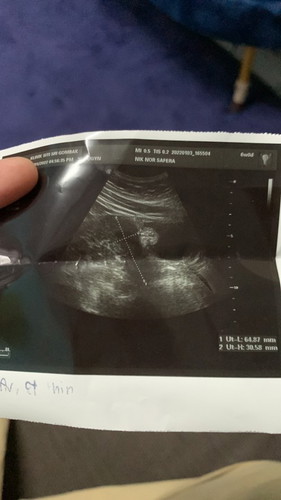

hi saya nak tanya, last period saya 22/11 so saya test upt pada 29/12 and naik double line walaupun samar yang second line. lepas dua hari saya buat lagi tetap samar. jadi 31/12 saya pergi klinik test upt naik satu line doc kata saya tak pregnant. 3/12 saya pergi scan dekat klinik lagi then result dia macam dekat dalam gambar. takde kantung tapi ada ketulan kecil. tapi saya cramp perut, sakit belakang, sakit pinggang dan loya loya. atau mungkin terlalu awal? kalau ikut week saya dah 6weeks camtu. boleh bagi saya pengalaman sesiapa yang pernah rasa macam saya tak?